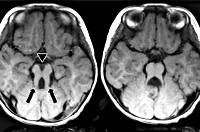

Самым типичным диагностическим признаком синдрома Жубер является наличие так называемого «симптома молярного зуба» - характерные изменения на МРТ головного мозга, внешне похожие на разрез зуба. Это проявление говорит о наличии нарушений формирования стволовых элементов мозга. Также на магнитно-резонансной томографии часто определяется недоразвитие червя мозжечка, гипоплазия мозолистого тела, гидроцефалия, расширение желудочков, энцефалоцеле и другие аномалии развития головного мозга. У взрослых больных синдромом Жубер нередко выявляются признаки поражения внутренних органов - поликистоз почек, фиброз печени, нарушения сердечного ритма. При осмотре у офтальмолога часто обнаруживаются непроизвольные аномальные движения глаз (нистагм), колобома, дистрофия и дегенерация сетчатки.